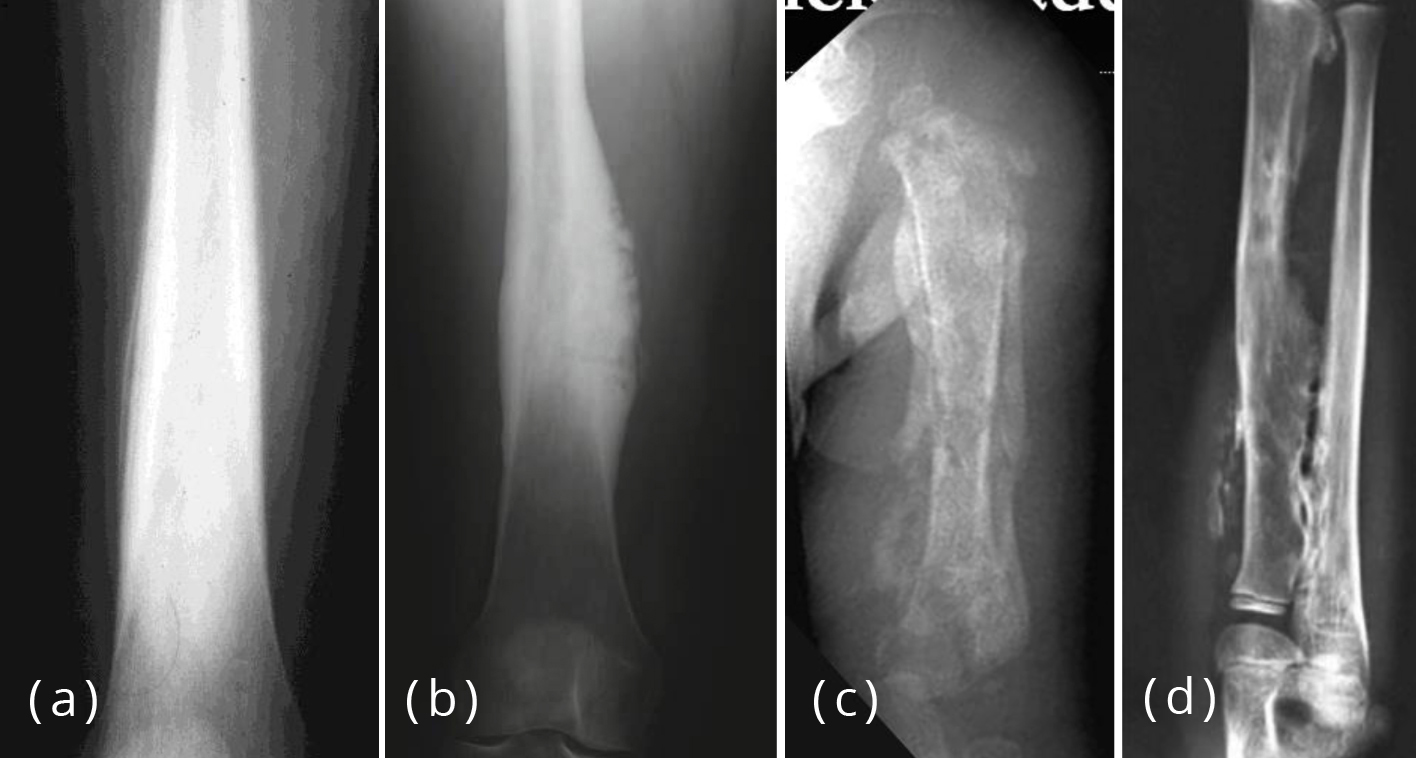

(A, B) The spiculated pattern of the periosteal reaction and Codman's Spiculated Periosteal Reaction Imaging findings include thin or thick irregular periosteal reaction and characteristic spiculated, frothy, or lacy appearance of the subperiosteum. Evaluation of focal bone lesions part i: Periosteal reaction is a nonspecific response by the host bone to the underlying lesion. As the periosteum is irritated, and potentially raised or disrupted by a bone lesion, the. Spicules of bone form perpendicular. Spiculated Periosteal Reaction.

Spiculated periosteal reaction exhibiting the divergent pattern in a Spiculated Periosteal Reaction Evaluation of focal bone lesions part i: Periosteal reaction is a nonspecific response by the host bone to the underlying lesion. Spicules of bone form perpendicular to the periosteal. As the periosteum is irritated, and potentially raised or disrupted by a bone lesion, the. Focal bone lesions fall into three broad categories: Imaging findings include thin or thick irregular periosteal. Spiculated Periosteal Reaction.

Spiculated periosteal reaction exhibiting the divergent pattern in a Spiculated Periosteal Reaction Parallel spiculated periosteal reaction (fig. Focal bone lesions fall into three broad categories: Periosteal reaction is a nonspecific response by the host bone to the underlying lesion. Spicules of bone form perpendicular to the periosteal. Imaging findings include thin or thick irregular periosteal reaction and characteristic spiculated, frothy, or lacy appearance of the subperiosteum. Evaluation of focal bone lesions part. Spiculated Periosteal Reaction.